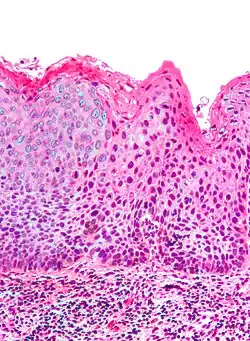

| Micrograph of (classic) vulvar intraepithelial neoplasia III. H&E stain. | |

Micrograph of vulvar intraepithelial neoplasia III. H&E stain.

Micrograph of vulvar intraepithelial neoplasia III. H&E stain. -